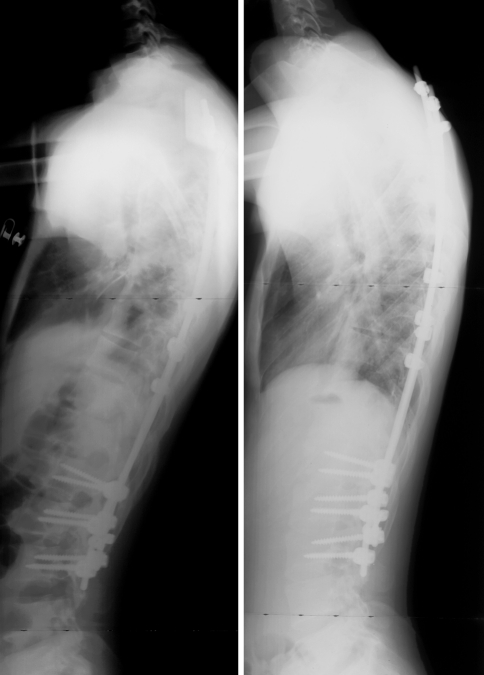

Fig. 6.

Lateral radiographs, preoperative and at latest follow-up (26 months), of a girl with a Lenke type 1 curve, operated at the age of 16 years. Five sublaminar UCs were used to instrument the main thoracic curve. The thoracic kyphosis was 14° preoperatively, and was improved to 40° after the procedure